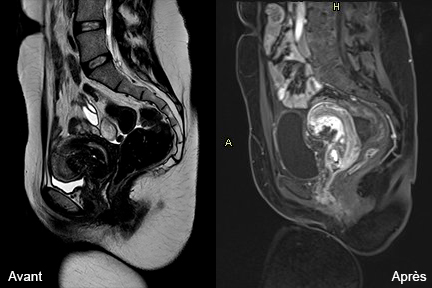

Notre service de radiologie interventionnelle propose désormais, en étroite collaboration avec le Centre liégeois d...